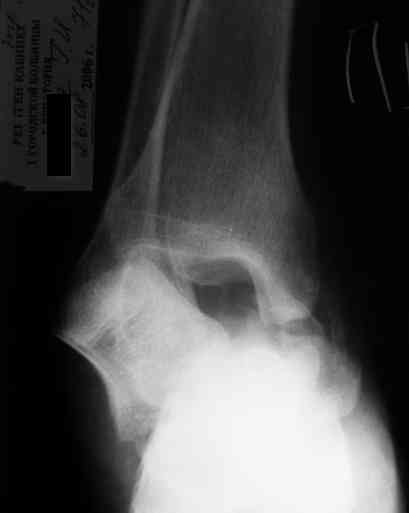

Re: Редкое повреждение - полный вывих тарана!

Уважаемый Александр! Как обещал представляю Р-граммы и операционные фото.